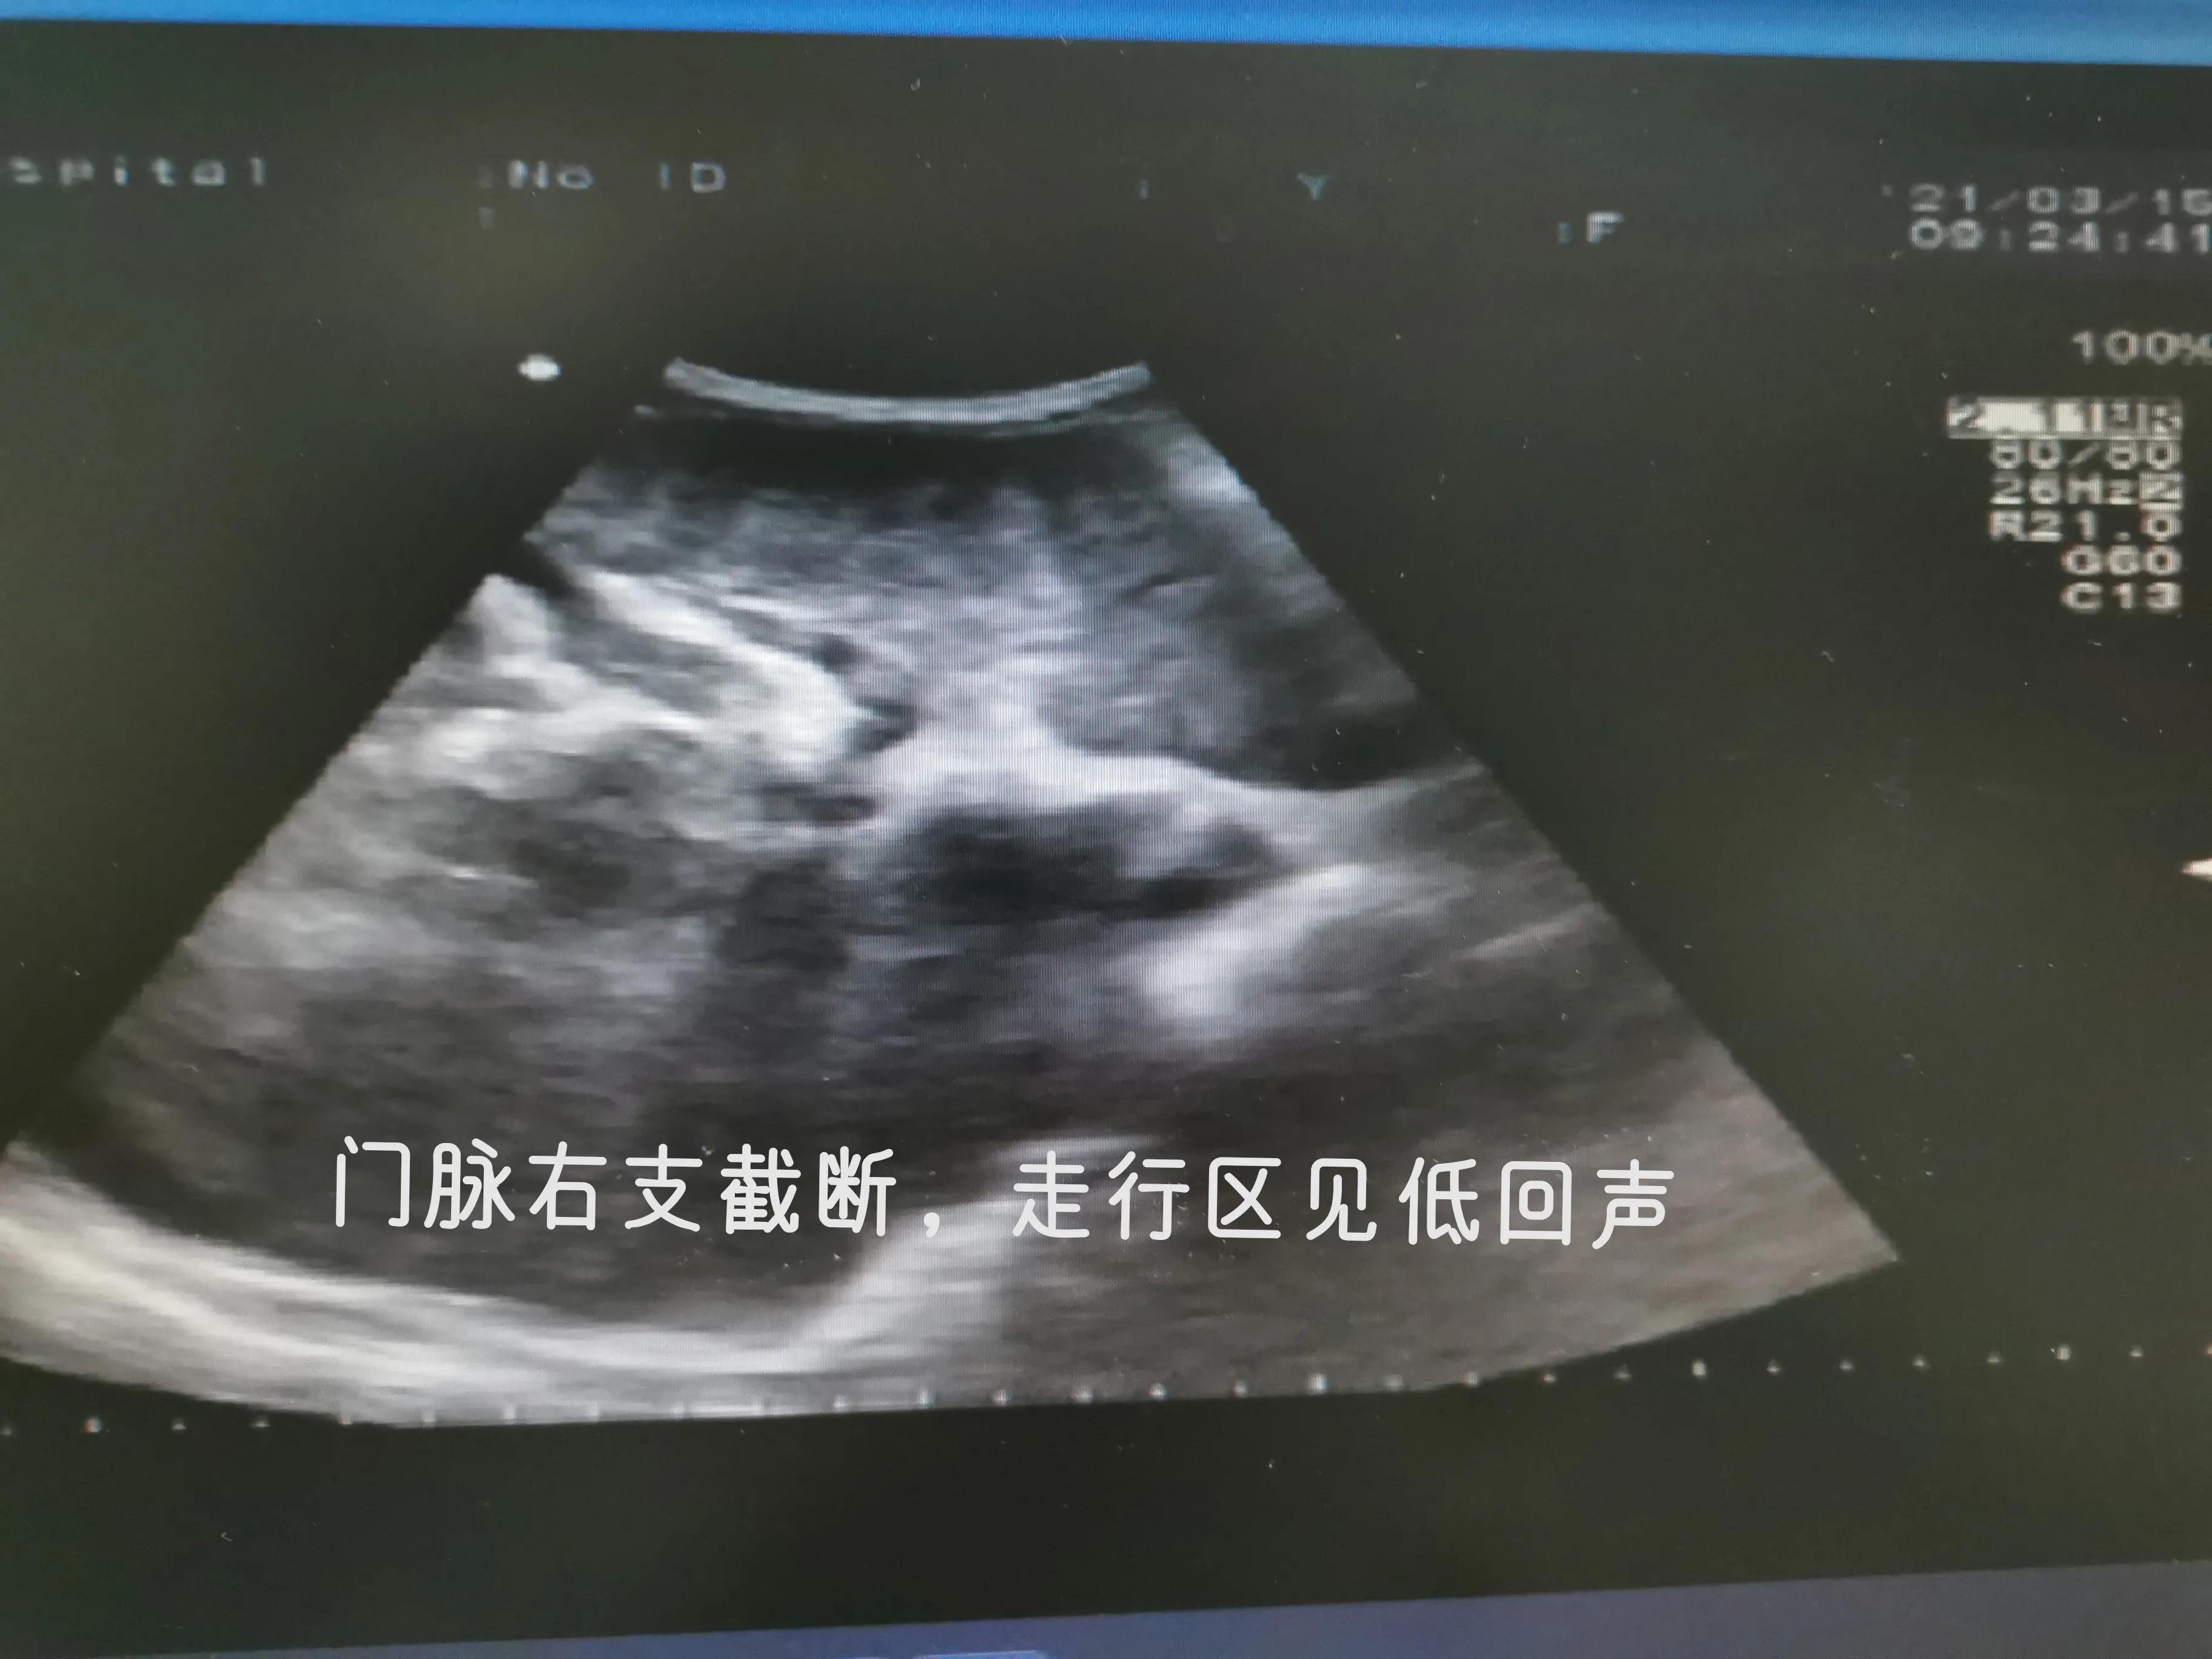

肝癌肿块

血管内癌栓形成